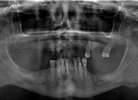

إغلاق المسافات بين الأسنان

الصور